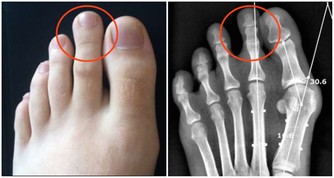

免疫力下降,有哪些症狀?

想要知道自己免疫力好不好,不妨簡單測試一下。如果以下表現佔了一半,該敲醒“警鐘”了~